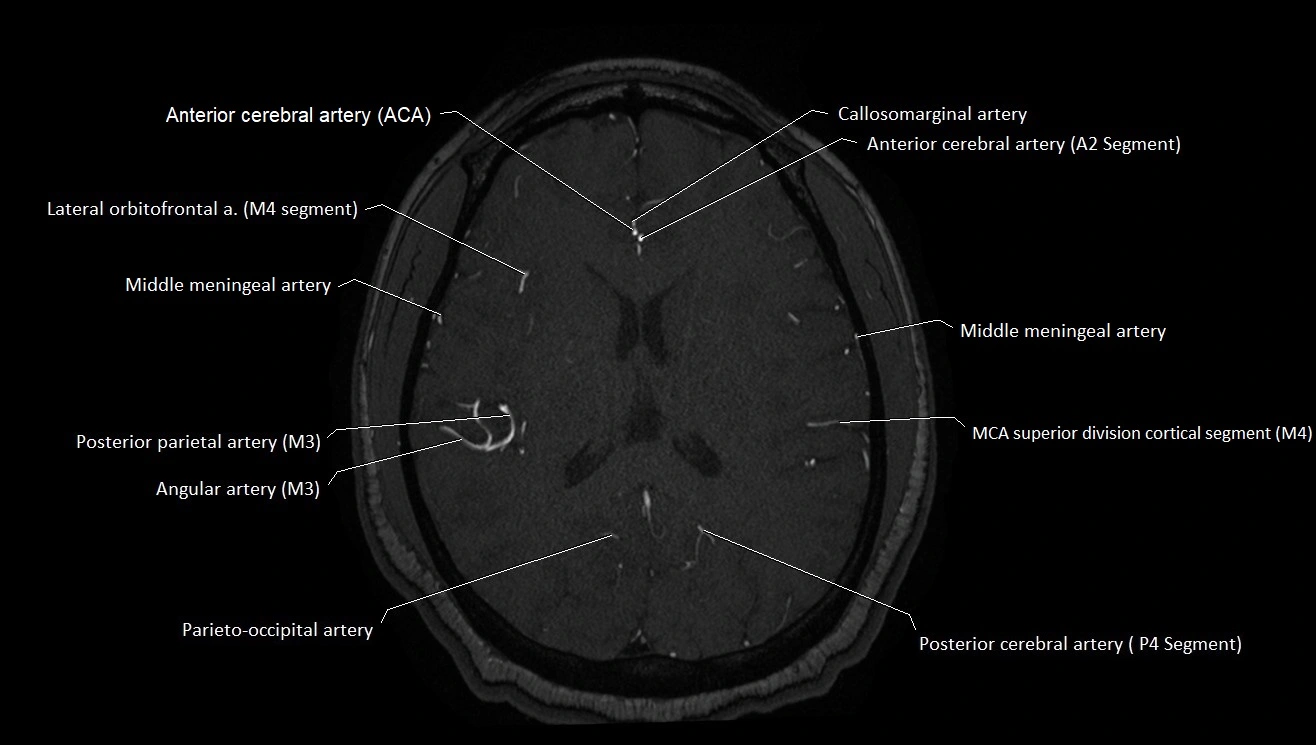

CT images

image